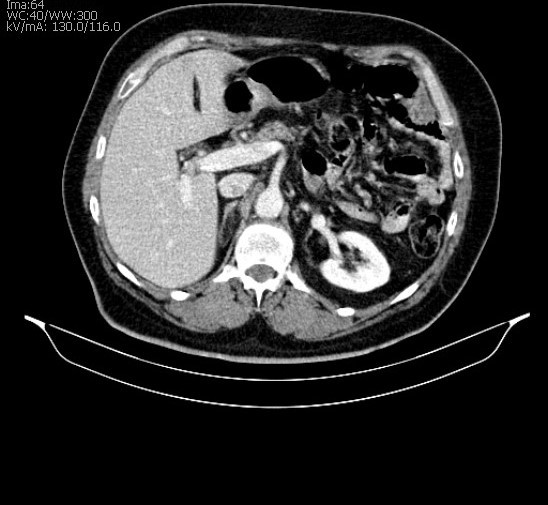

Exames de tomografia são muito confiáveis e seguros, realizados por aparelho de raios X de alta resolução que gira em torno do corpo, fazendo radiografias transversais. É capaz de obter imagens em fatias do corpo, gerando imagens tridimensionais. O exame é indolor, o paciente deve permanecer imóvel e é de rápida duração.